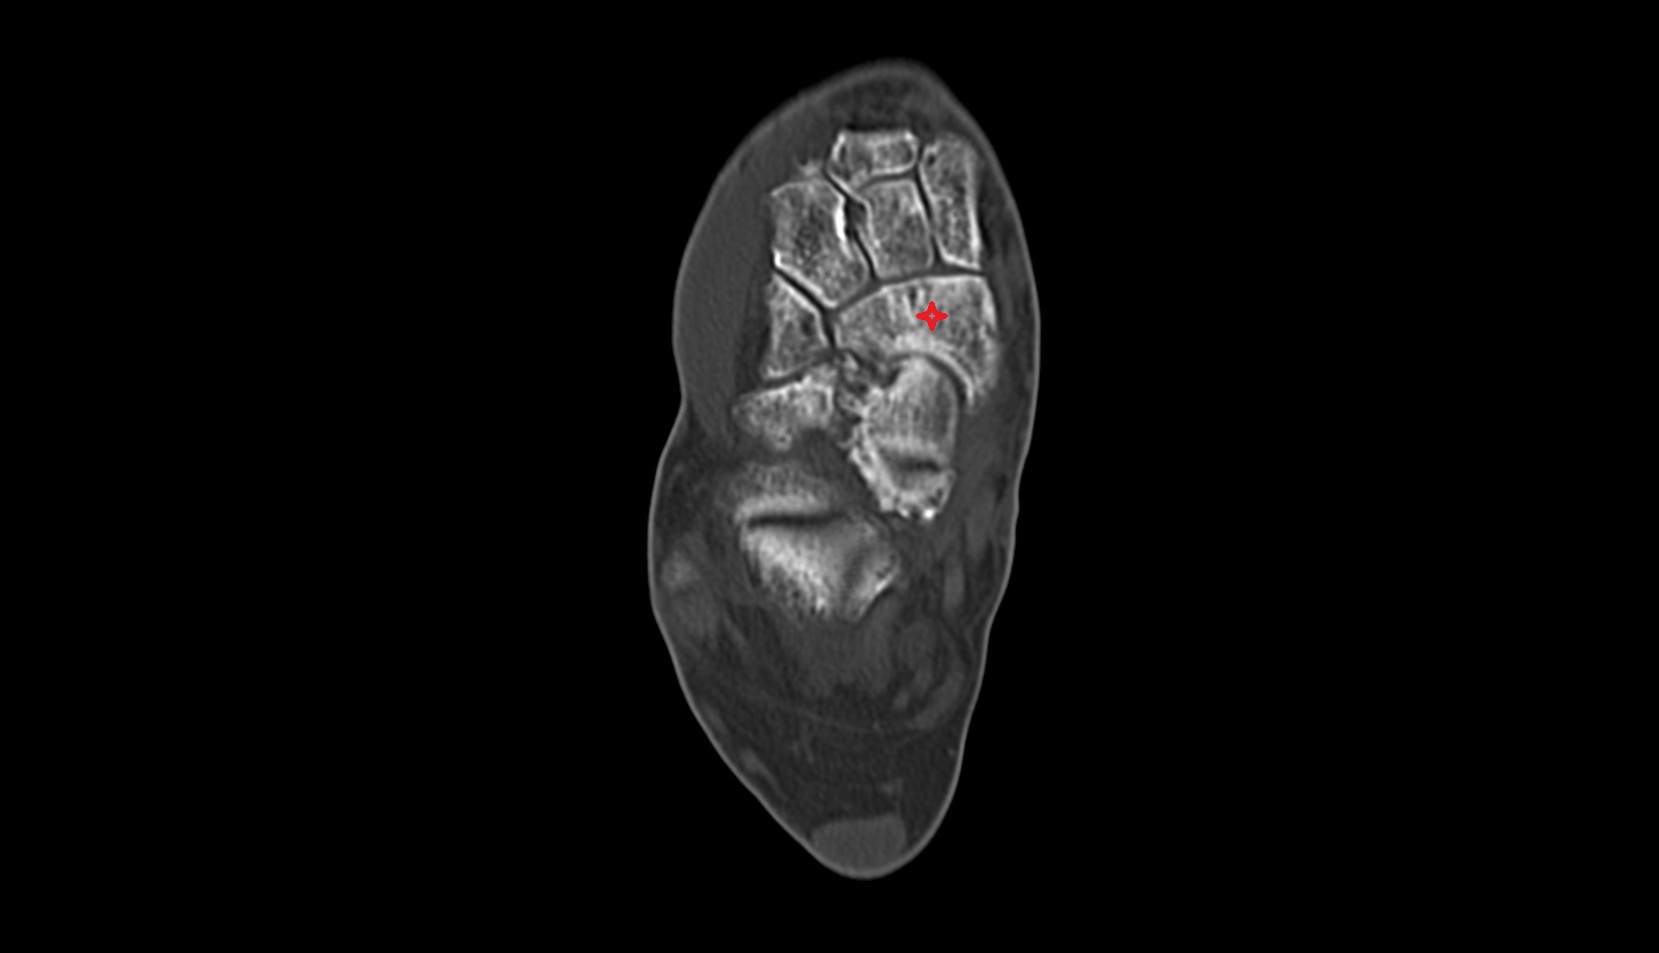

- Talus

- Head of talus

- Body of talus

- Neck of talus

- Calcaneus

- Sustentaculum tali

- Cuboid

- Lateral cuneiform bone

- Medial cuneiform bone

- Intermediate cuneiform bone

- Interosseous membrane (middle tibiofibular ligament)

- Navicular bone